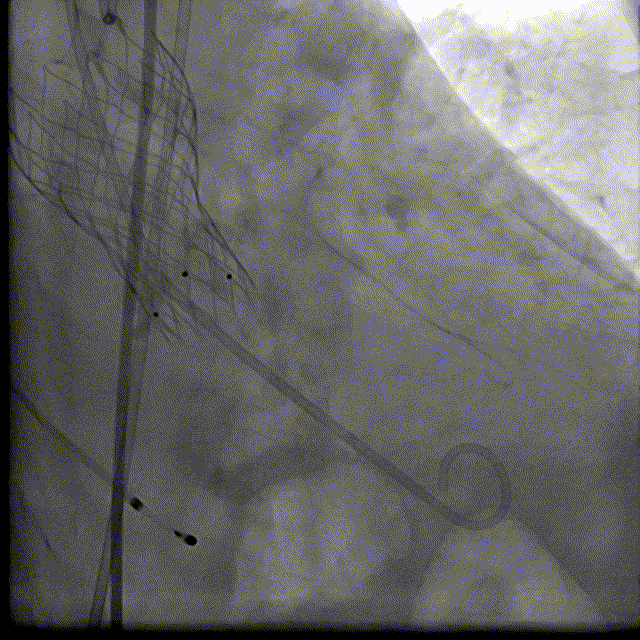

根部解刨:

手术过程